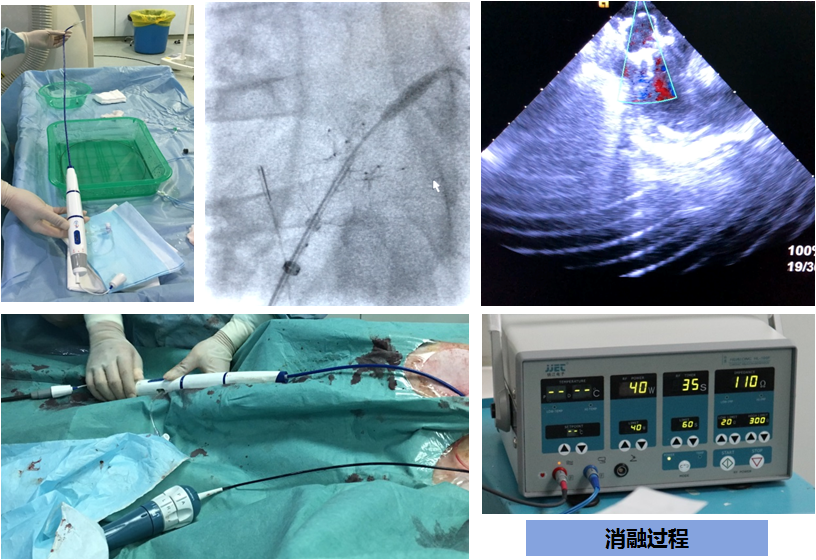

手术过程